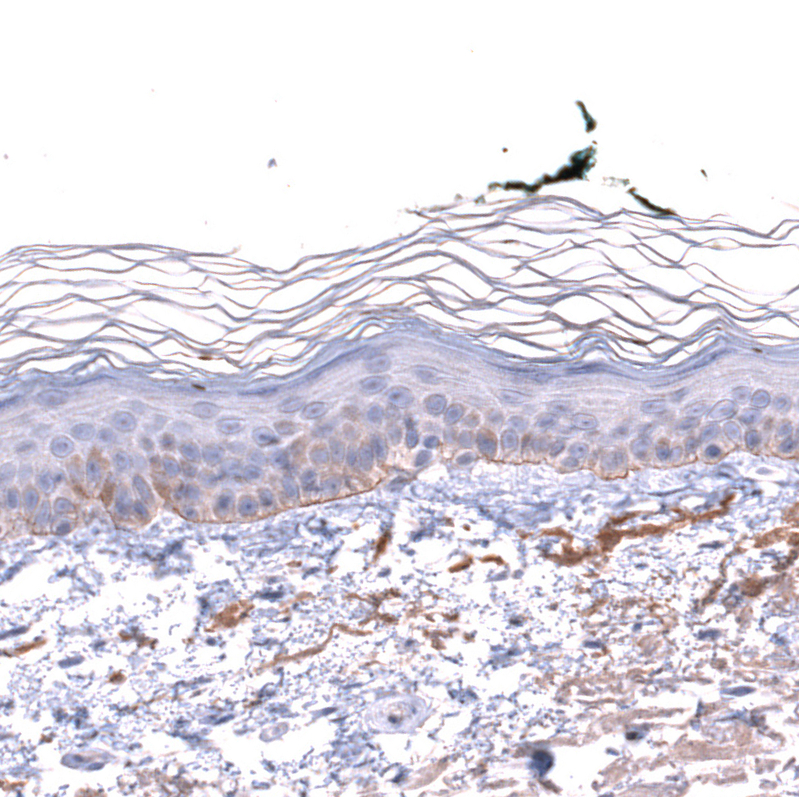

Immunohistochemical staining of human skin shows moderate positivity in basement membrane of epithelial cells.